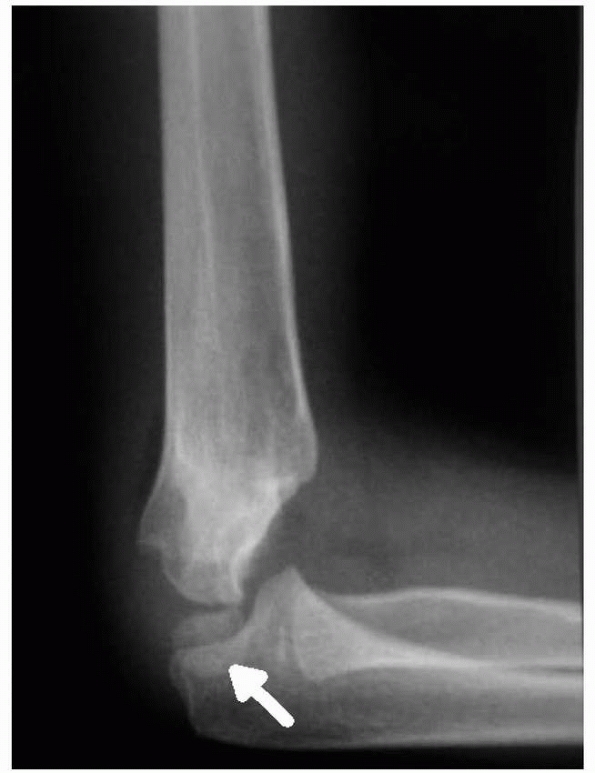

humeral tenderness and restriction of motion, particularly lack of full

extension. Radiographs may be negative except for a posterior fat pad

sign. In type III fractures, gross displacement of the elbow is evident

(Fig. 14-9).

![]() |

FIGURE 14-8

Note the lateral view does not show significant displacement. This view alone would suggest nonoperative treatment may be sufficient. (Reproduced with permission of Children’s Orthopaedic Center, Los Angeles,CA.) |